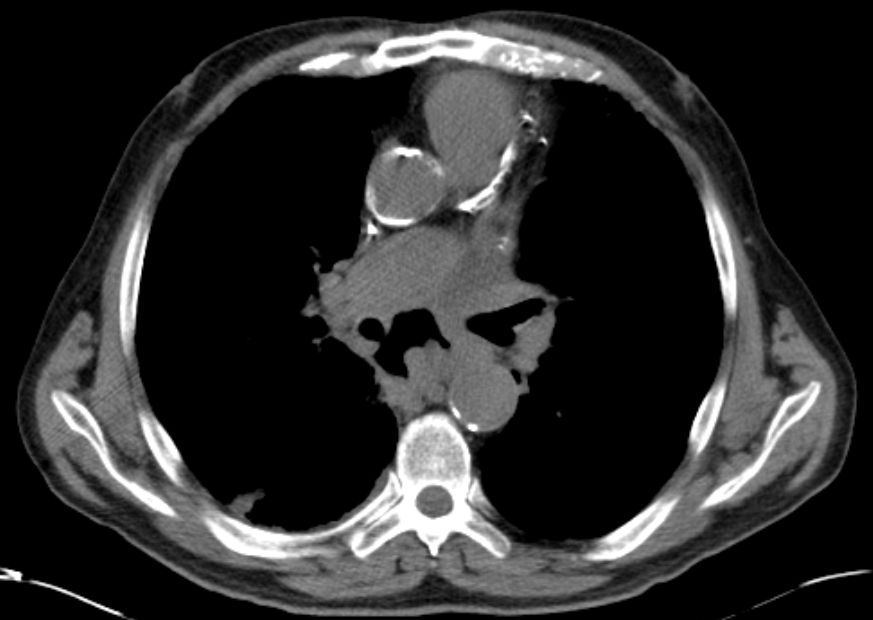

CT Infiltration des oberen Mediastinums. Flottierender Thrombus in der Vena cava superior.